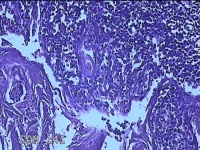

性别

女

年龄

7岁

鼻塞、咽异物感、打鼾、张口呼吸伴睡眠呼吸暂停2年。

双侧扁桃体

灰白粉红色扁桃体3.3x2.3x0.3cm两个,表面均有部分糜烂,切面灰白粉红色,结节状,质软。